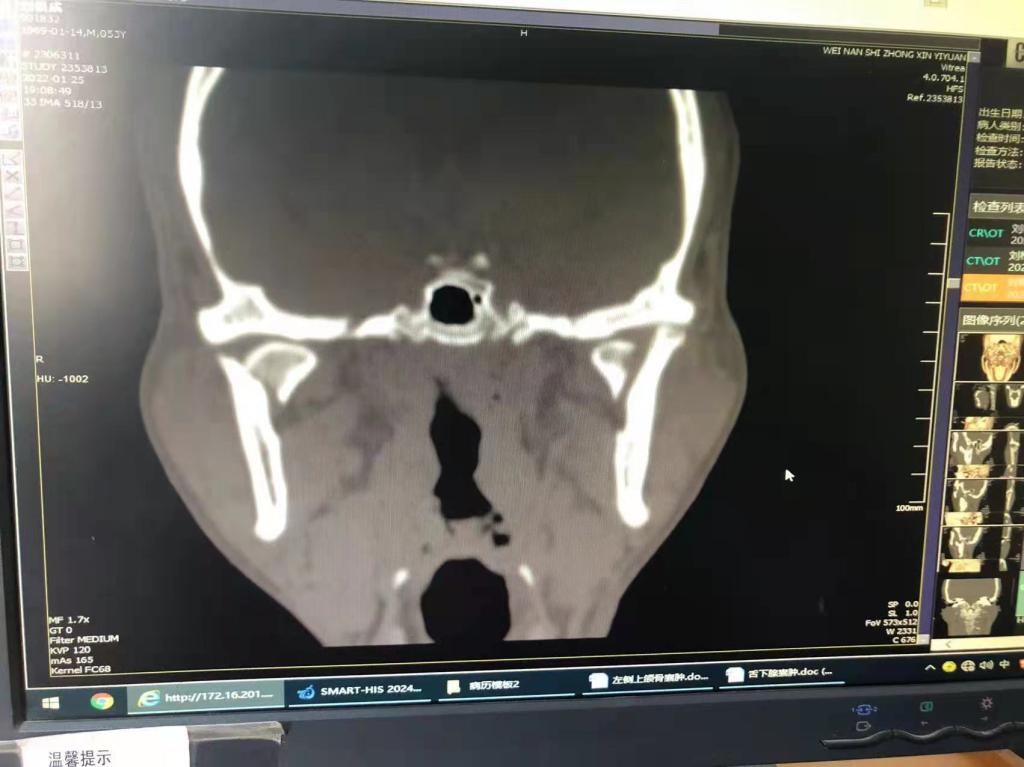

据了解,53岁的患者刘先生在1月25日当天走路不慎摔倒致下颌损伤,造成颏部软组织裂伤和张口困难,前往当地卫生院进行颏部裂伤清创缝合术。术后辗转到MILAN.COM口腔科门诊就诊,并进行颌面部CT检查提示为下颌颏部正中和双侧髁状突骨折,双侧下颌升支高度不一致,右侧较左侧变短1cm,张口重度困难,咬合关系错乱。刘先生因考虑在春节过后再入院治疗,于2月8日再次前来口腔科以“下颌骨骨折”收治人院。

口腔科主治医师蔺非非为患者入院后进行完善术前常规检查和颌间牵引恢复咬合关系。科主任李瑞春结合患者实际病情和检查结果认为,患者的髁突骨折在下颌骨骨折中所占比例较高,约为17.0%-36.3%。髁突骨折时,耳前区有明显的疼痛,局部肿胀、压痛。通过手指深入外耳道或在髁突部触诊,如张口时髁突运动消失,可能有骨折段移位。双侧低位骨折时,2个髁突均被翼外肌拉向前内方,双侧下颌支被拉向上方,可出现后牙早接触,前牙开秴。髁状突骨折易引起下颌后缩,张口困难,咬合关系错乱,关节强直等并发症。考虑患者系陈旧性骨折应尽早实施手术,避免骨折导致的张口困难、关节强直等并发症。因患者已经错过最佳治疗时期,决定尽快为患者进行手术治疗。

科主任李瑞春和主治医师蔺非非经过缜密的术前讨论和充分评估,手术在全身麻醉下进行,术中克服术野狭小操作不便困难,将下颌骨骨折完好对位,顺利地完成了"双侧髁状突和下颌颏部正中骨折切开复位内固定术"。术后检查患者面部对称,双侧下颌升支高度一致,咬合关系已恢复。